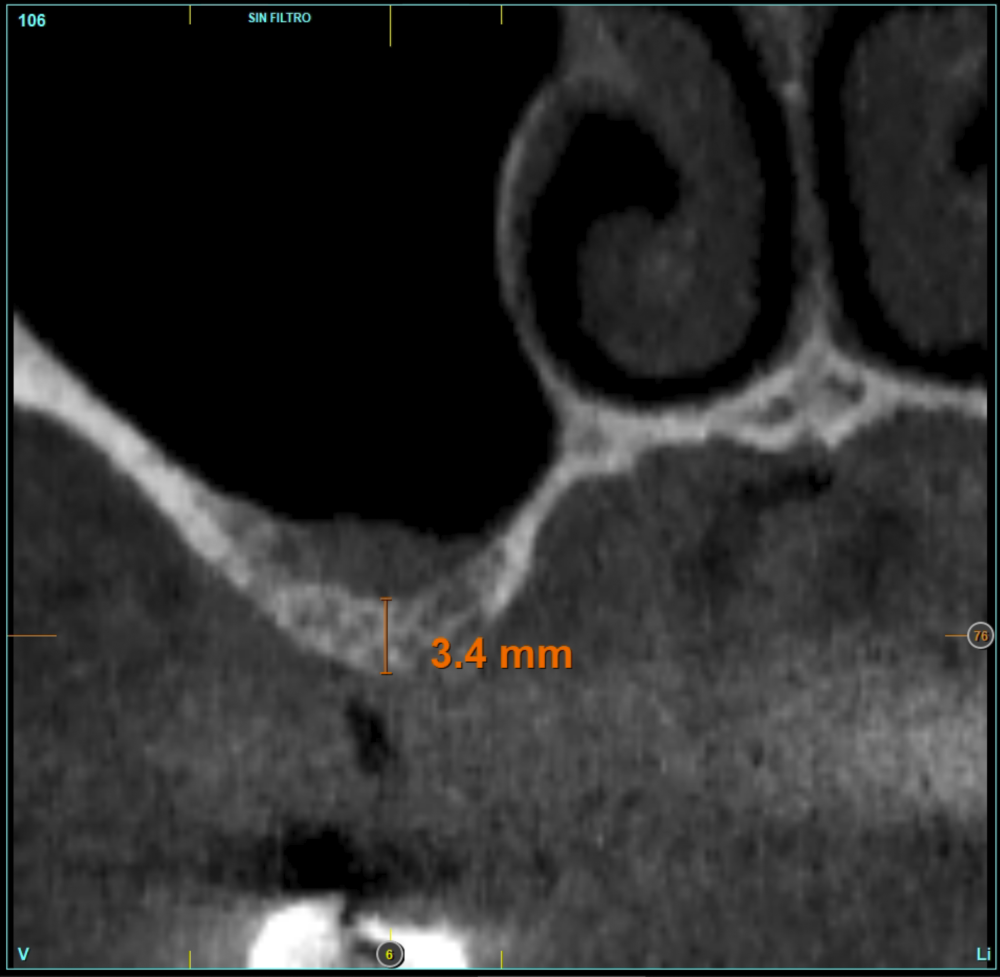

Material and method. A retrospective study has been carried out in patients in whom extra-short implants (4.5 and 5.5 mm length) were inserted directly by transcrestal elevation with residual ridges between 2 and 3 mm. The implant was the analysis unit for the descriptive statistics regarding location, implant dimensions, and radiographic measurements. The patient was the measurement unit for the analysis of age, sex and medical history. The main variable was the gain in height over the apex of the implant after 6 months of the surgery and one year after the load comparing both measurements and as secondary variables the biological complications and the implant failure were recorded.

Results. Ten patients who met the inclusion criteria were recruited and 20 implants were inserted. The mean residual bone volume height was 3.1 mm (+/- 0.3 mm with a range elevation above the apex of the implant in millimetres is of 2.8 mm (+/- 0.99 range 1.9 -5 mm). In the control cone-beam after one year of the studied load of the implants, the bone gain achieved was maintained, with no decrease in the volume gained, only three cases showed a decrease of between 0.4 and 0.5 mm of the initial volume at the end. No implants failed in the follow-up period and no biological complications were found in the surgery.